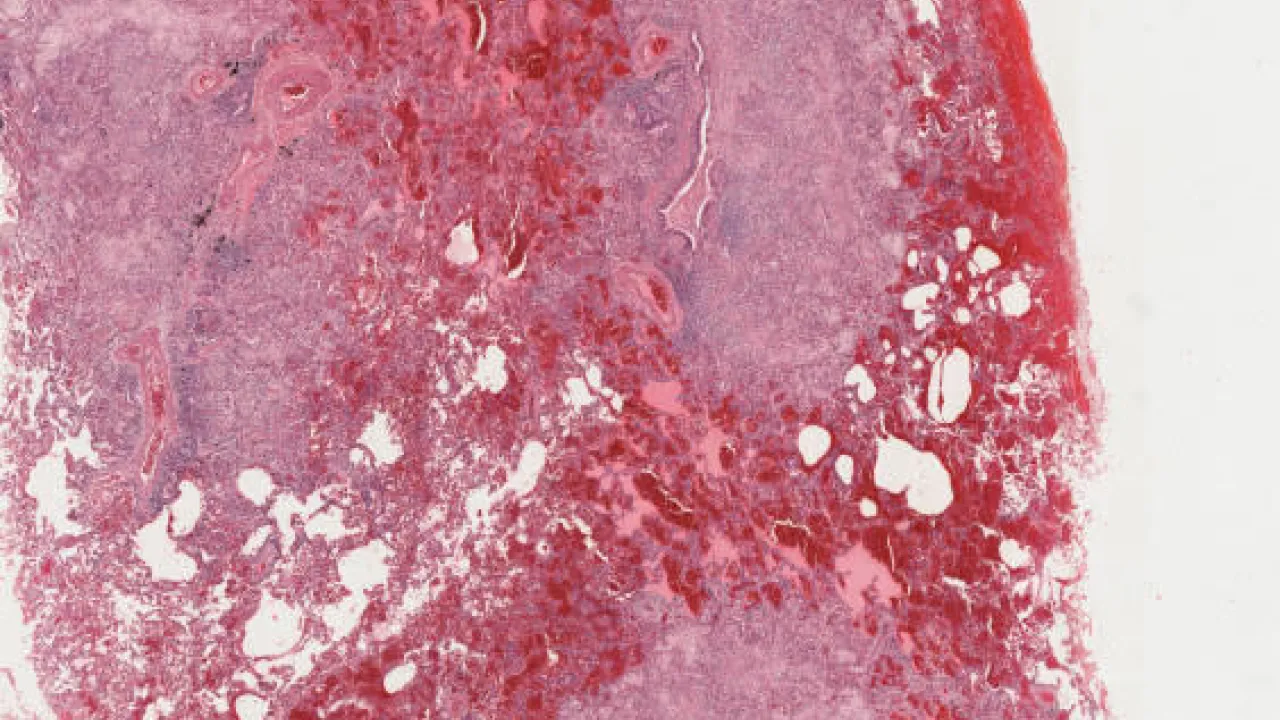

Testis, Mixed germ cell tumour